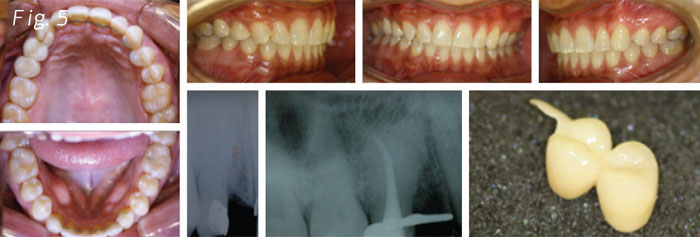

Making a close diagnosis on the right upper bicuspid area, we found a problem of hypercementosis on the second bicuspid. This forced us to make changes to the original treatment plan of placing an implant and taking a closer view. We had to work with the periodontics, prosthodontics and endodontics. Considering the mentioned outcomes, the decision of performing the root canal and building a flying bridge that would hold on to the second right upper bicuspid with the hypercementosis and leave a little extension to the cuspid, was taken (Fig. 5).

We can take advantage of a hypercementosis tooth as an anchorage unit for building a bridge. In this case, with the limitation of not having a space for the implant because the problem was mesial to the second bicuspid root.